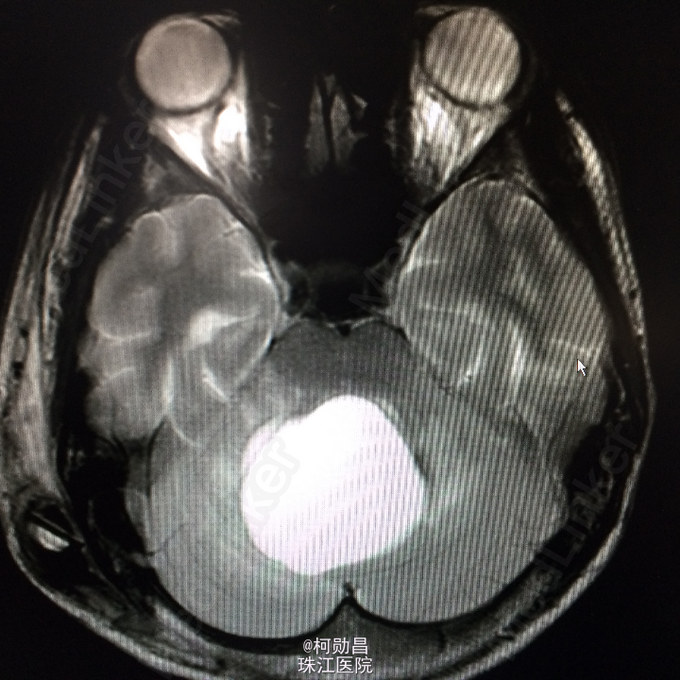

患者17岁男性,因“发现后颅窝占位1周”入院, 于1月前无明显诱因出现头晕、头痛,伴呕吐、肢体抽搐及行走不稳,无肢体乏力、意识障碍、视物模糊等,间至当地医院治疗,症状可缓解,1周前出现上述症状加重,遂至当地医院治疗,行头颅CT提示:后颅窝占位、梗阻性脑积水。后入我院,行手术治疗。病理结果提示:血管母细胞瘤